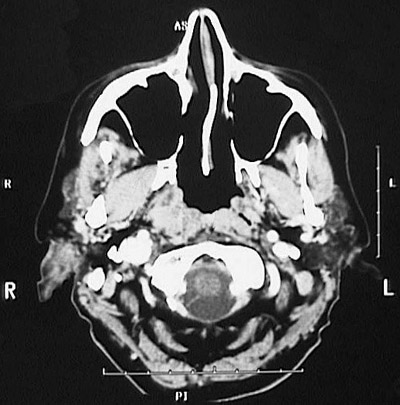

This head CT scan with contrast seen in axial view above demonstrates a 3 cm nasopharyngeal carcinoma on the right between the pterygoid plate anteriorly and the prevertebral and right carotid space posteriorly. In the coronal view below, this nasopharyngeal carcinoma is also seen.